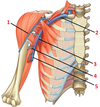

1: Trapezius muscle

1?

1: Cranial nerve XI (accessory nerve)